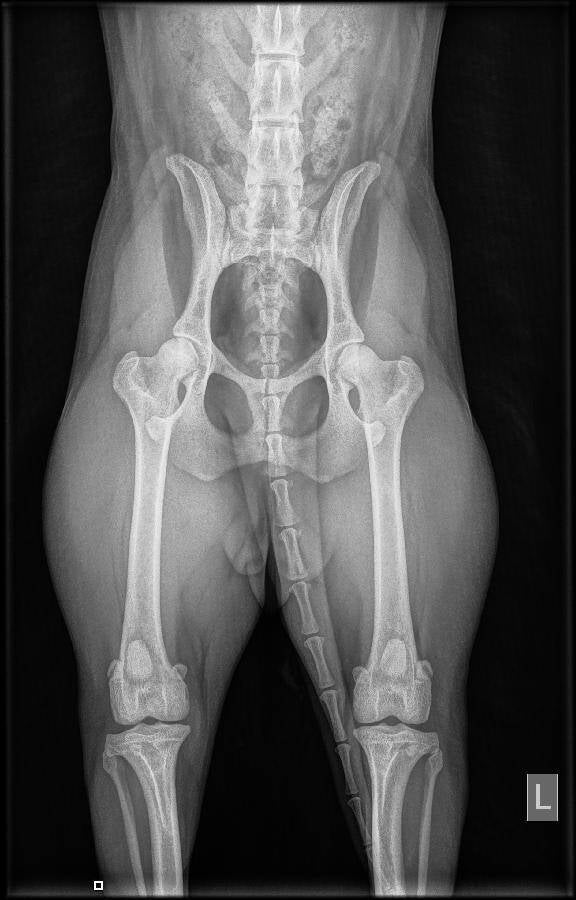

Uitslag heupen Mayla

Mayla 4 september 2019 heupen HD A